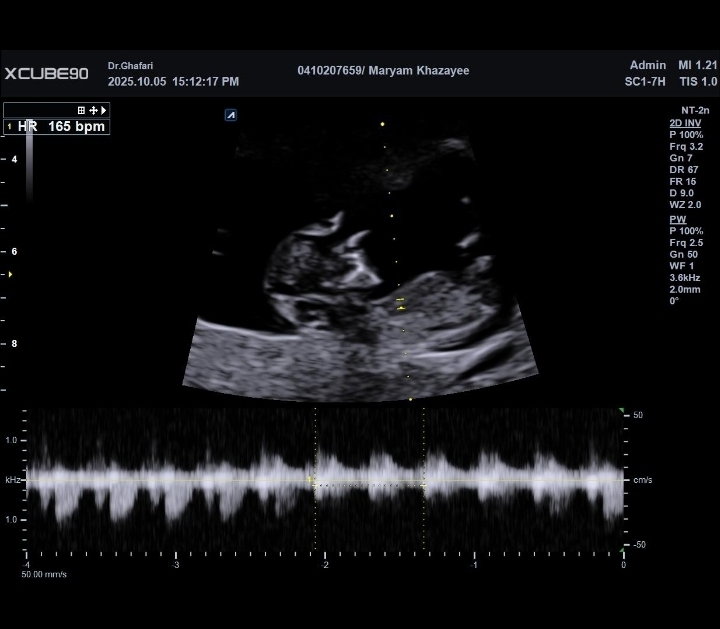

سلام ممنون میشم سونو من رو تفسیر کنید

و اینکه براساس تصویر تصویر به نظرتون دختره یا پسر ؟

ممنون که نظرتون رو گفتید اتفاقا دکتر هم گفت احتمال ۶۰ درصد پسر باشه گفتم نظر دوستانی که اینجا هستن رو هم بپرسم

من ورامینم سونوگرافی دکتر غفاری رفتم

سلام به روی ماهتون مامان جان

برای تعیین جنسیت باید منتظر سونو آنومالی اسکن باشیم

همه چیز عالی است و مشکلی ندارد فقط جهت تفسیر صحیح باید منتظر بخش خون غربالگری باشیم مبارکتان باشد